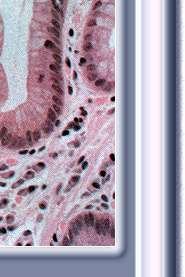

Barrett01.jpg